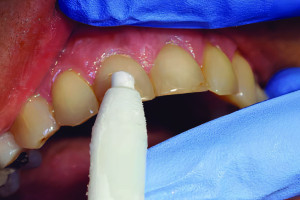

Трудности в лечении этого зуба связаны с тем, что его мезиодистальная ширина намного меньше (Рис. 1А) по сравнению с вестибулярно-язычной шириной (Рис. 1В), что делает очень трудным, если не невозможным, расширение канала или каналов полностью в любом направлении.

Рисунок 1. A. Нижний центральный резец. Обратите внимание на малую мезиодистальную ширину корня. B. Корень того же зуба значительно шире в вестибулярно-язычном направлении. Обратите также внимание на вогнутость на уровне средней трети.